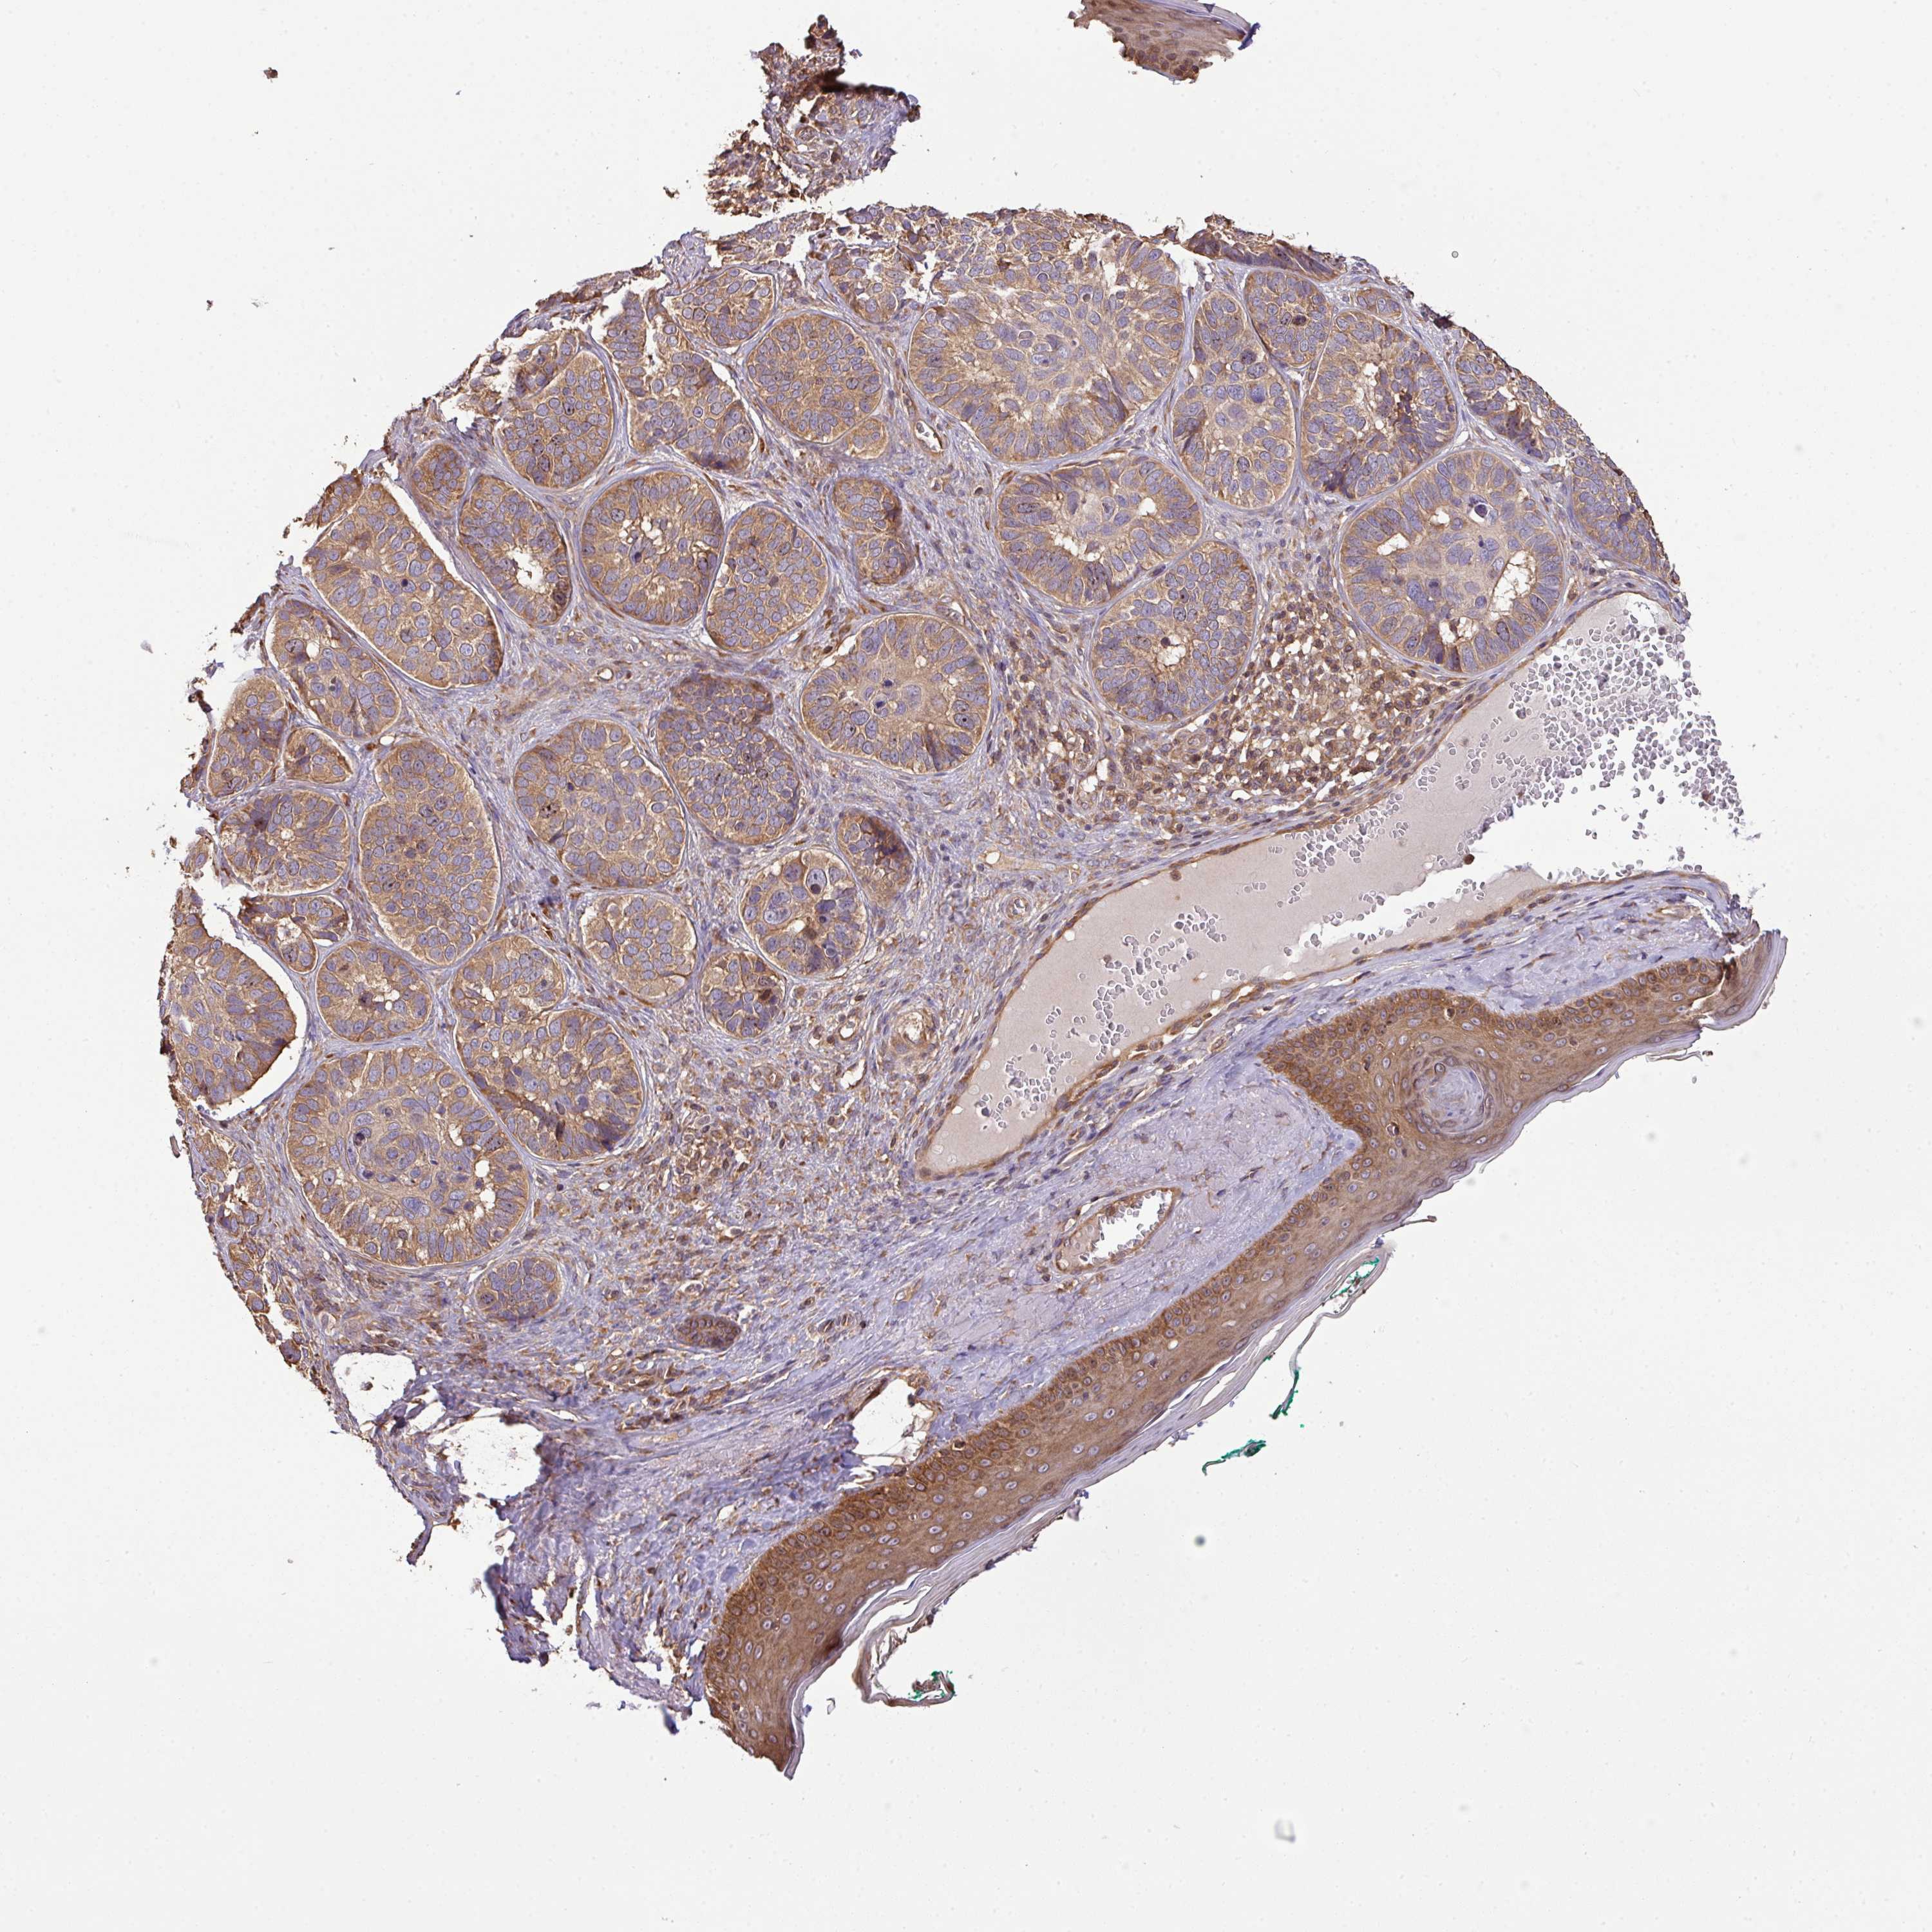

SKIN CANCER - Protein expressioni

A mouse-over function shows sample information and annotation data. Click on an image to view it in a full screen mode. Samples can be filtered based on level of antibody staining by selecting one or several of the following categories: high, medium, low and not detected. The assay and annotation is described here.

Antibody stainingi

Antibody staining in the annotated cell types in the current human tissue is reported as not detected, low, medium, or high, based on conventional immunohistochemistry profiling in selected tissues. This score is based on the combination of the staining intensity and fraction of stained cells.

Each image is clickable and will lead to virtual microscopy that enables deeper exploration of all samples and also displays staining intensity scores, fraction scores and subcellular localization as well as patient and tissue information for each sample.

Antibody HPA050955

Staining

High

Medium

Low

Not detected

Intensity

Strong

Moderate

Weak

Negative

Quantity

>75%

75%-25%

<25%

None

Location

Nuclear

Cytoplasmic/membranous

Cytoplasmic/membranous,nuclear

Basal cell carcinoma